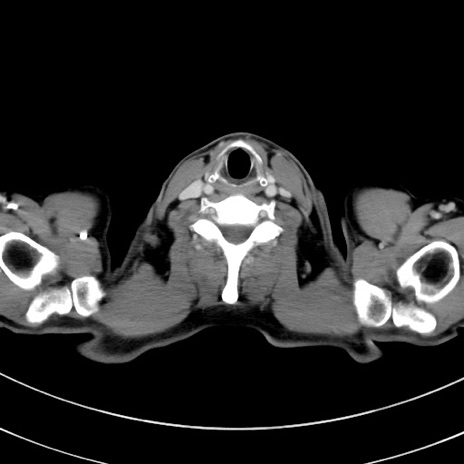

症例8(横断像)

【症例】 60歳代男性

【主訴】 黒色吐物

【現病歴】 4日前から嘔気自覚、2日前の朝食後にも嘔気あり、自分で手で嘔吐反射起こし嘔吐したところ血が混ざっていたため受診。

【既往歴】 5年前汎発性腹膜炎を伴う急性虫垂炎で手術、高血圧、前立腺肥大症、高脂血症

【身体所見】 腹部正中に手術癩痕あり 腹部平坦・軟圧痛なし膨満感あり

【データ】WBC 8400、CRP 4.54